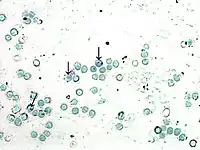

| Iniciar el conteo. Las células rojas toman una coloración grisácea verdosa. El RNA presente en los reticulocitos se colorea de azul intenso. |

La eritropoyésis efectiva se determina por el recuento de reticulocitos en sangre periférica,[2] el cual se expresa en valor relativo o porcentual (número de reticulocitos por 100 células rojas) y en valor absoluto (total de reticulocitos circulantes por cada milímetro cúbico (mm³) de sangre). El conteo de reticulocitos se puede dar por tinción con un colorante especial para reticulocitos (Azul de cresil brillante) de naturaleza basofila y por el cual las mitocondrias y ribosomas tendrán afinidad y los mostrara en el frotis de un color azul moteado.

En microscopía electrónica es fácil de reconocer por su superficie irregular, con invaginaciones y presencia de múltiples orgánulos como: mitocondrias, pequeño número de ribosomas, remanentes del aparato de Golgi y protoporfirina. Al microscopio de luz se identifica mediante coloraciones supravitales (azul de cresil brillante, nuevo azul de metileno). El colorante se absorbe y el ARN y los demás orgánulos citoplasmáticas se precipitan como sustancia reticulofilamentosa, visible en los extendidos secos, como gránulos amorfos intracelulares que se tiñen de azul profundo.

Coloreado con Wright o Gimsa, el reticulocito se identifica por su basofilia difusa llamada policromatofília y por ser una célula ligeramente más grande que el eritrocito. La célula debe poseer al menos dos gránulos de precipitado bien definidos y separados de la membrana para considerarla reticulocito.